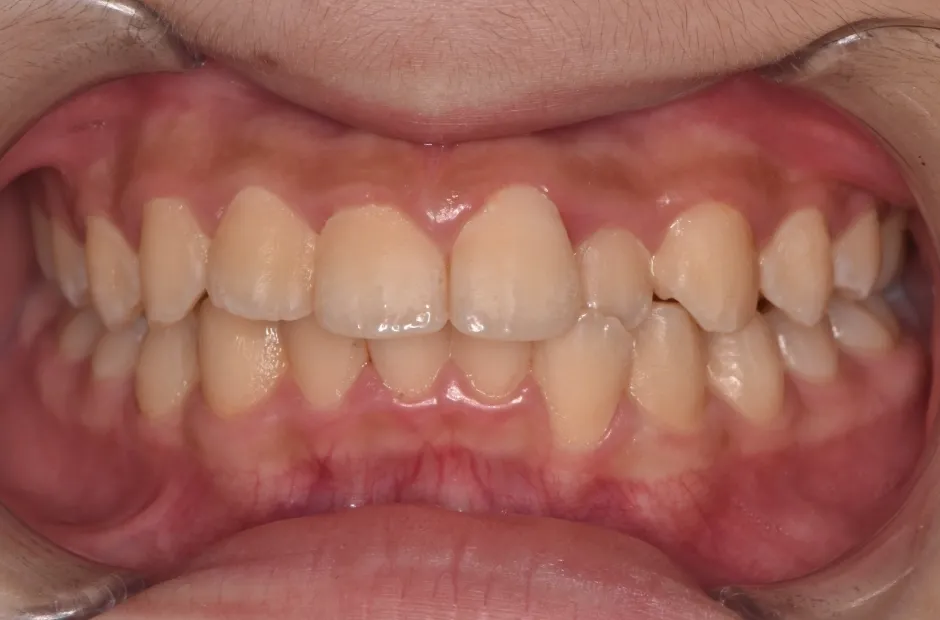

反対咬合

| 診断名・主訴 | 前歯反対咬合 |

|---|---|

| 年齢・性別 | 12歳・男性 |

| 治療期間・回数 | 1年半 18回 |

| 治療に用いた主な装置 | リンガルアーチ(前方誘導弾線) |

| 抜歯部位 | なし |

| 治療費 | 35万円(税抜) |

| リスク・副作用 | 装置による違和感・疼痛・歯肉退縮・歯根吸収・虫歯のリスクなど |

リンガルアーチ

| 診断名・主訴 | 反対咬合 |

| 年齢・性別 | 14歳・女性 |

| 治療期間・回数 | 2年6か月 |

| 治療に用いた主な装置 | リンガル |

| 抜歯部位 | 上顎5,5 下顎4,4 |

| 治療費 | 100万円(税抜) |